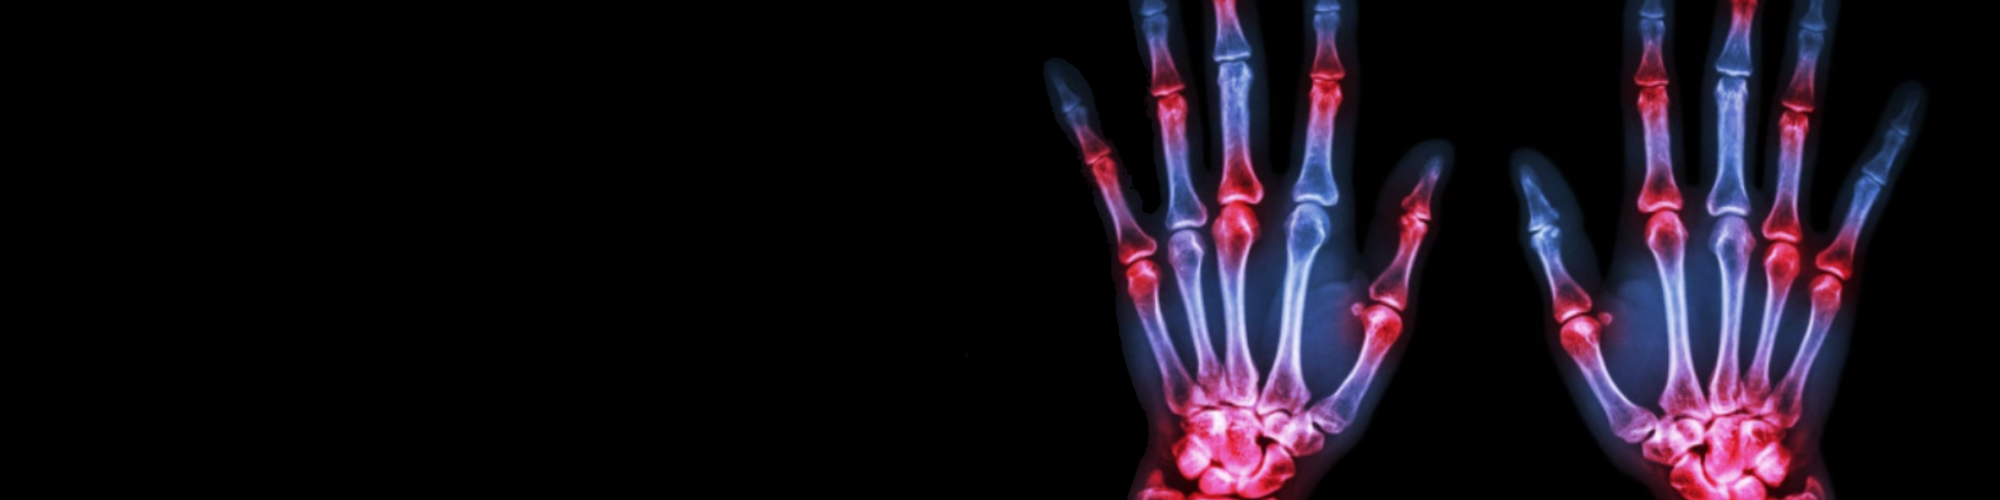

Des Arthrites Autoimmunes à ARTHEMIS : ARTHritEs, Microchimérisme et InflammationS

Cette unité décortique les mécanismes qui provoquent des arthrites autoimmunes en englobant de façon plus visible les thématiques développées depuis 20 ans relatives au microchimérisme.

ARTHritidEs, Microchimerism and InflammationS